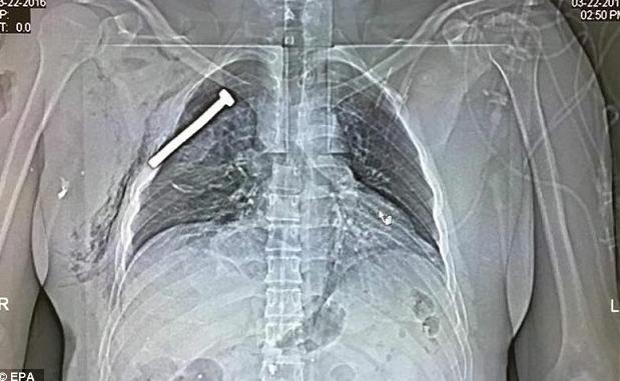

Hetimet kanë treguar se të paktën një nga bombat e shpërthyera sot në aeroportin e Brukselit ishte nga ato që cilësohen si “bombë me gozhdë”.

Kjo bombe mbushet me pjesë metalike (vida ose gozhdë) që pas shpërthimit, këto të godasin personat e paprekur nga vala e saj duke u shkaktuar plagë të rënda, deri edhe vdekjen.

Zbulimi është bërë teksa një prej të plagosurve iu nënshtrua një skaneri ditën e sotme në Spitalin Ushtarak në Himbik, ku afër zemrës së tij u gjend një vidë të paktën 5.5 cm të gjatë.